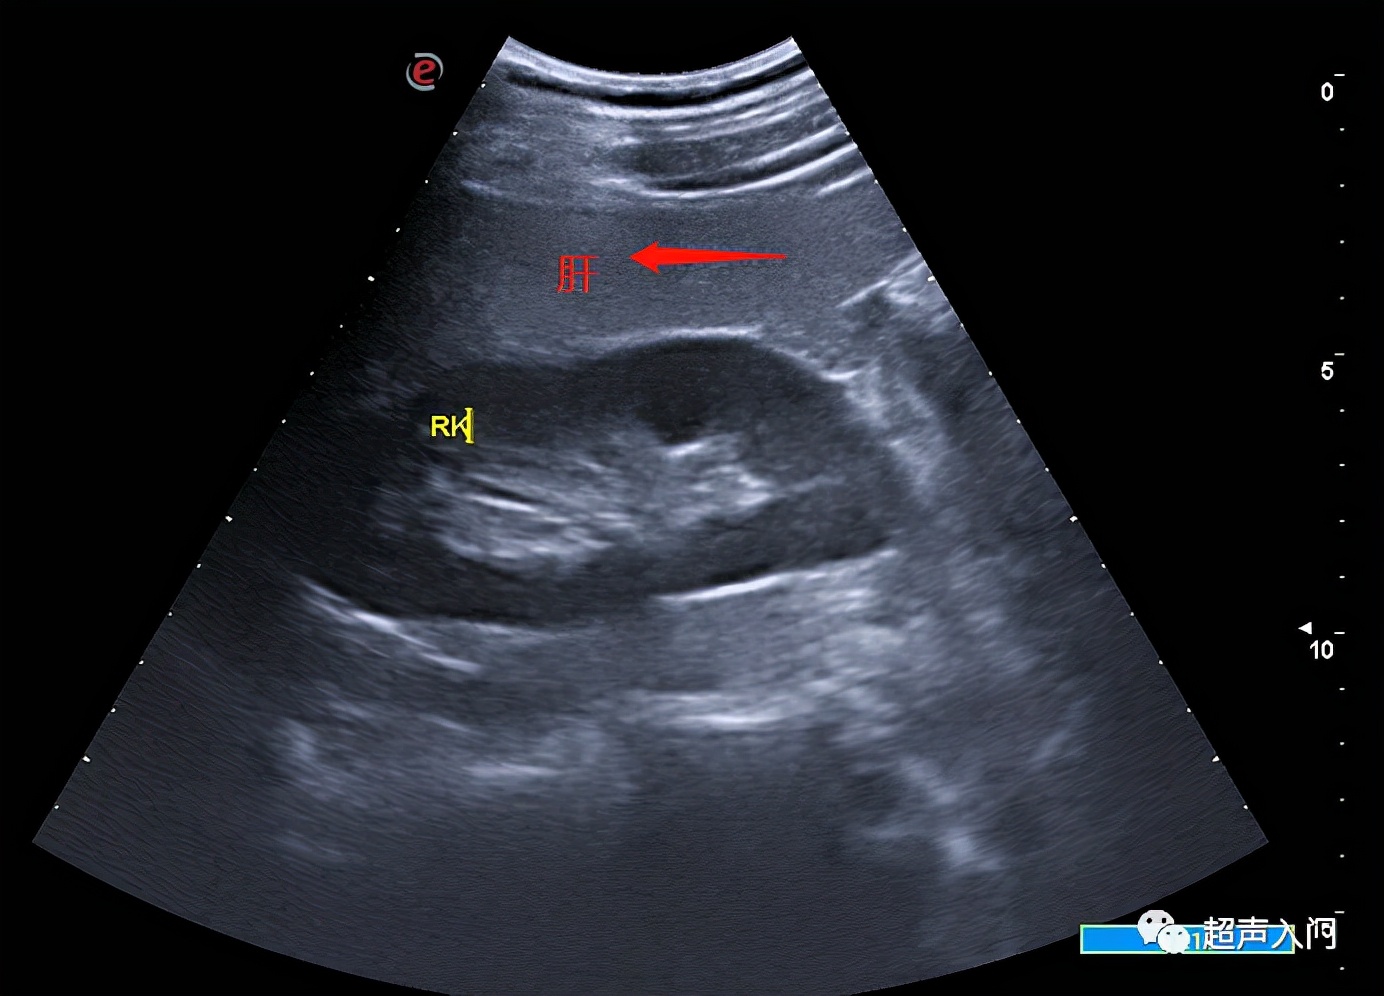

07 胆囊结石

(瞅见那不省心的玩意儿了吗?)